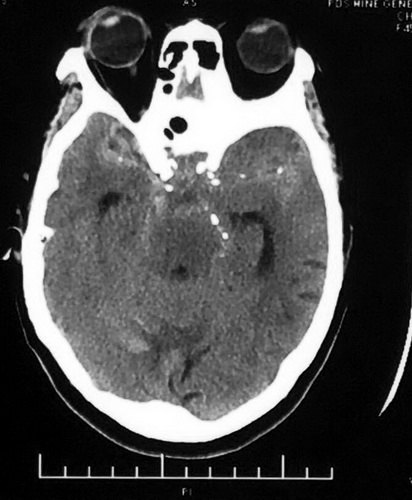

一、病例特点: 患者68岁,女性 、急性起病,因“突发恶心呕吐3天”入院。 通过查体:患者一般状况较差,血压最高188/109mmHg,其余生命体征基本平稳。神志模糊,失语,查体欠合作。双侧瞳孔等大等圆,左:右=3:3mm,对光反射灵敏。颈抵抗2横指,克氏征阳性。左侧肢体刺激可动,右侧肢体肌力0级,右则肢体肌张力中度增高。深浅感觉无法检查,右侧浅反射减退,双侧病理征可疑阳性。入院后完善相关检查。CT提示以基底池为主的蛛网膜下腔广泛高密度灶,考虑为SAH,同时存在脑积水 ,出血。

二、诊断:破裂性右侧大脑后动脉瘤,合并基底动脉顶端动脉瘤。